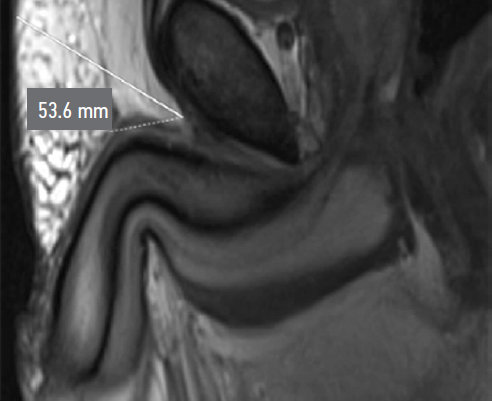

During preoperative assessment, penile length was recorded in both the flaccid and stretched states (median: 6.75 cm and 12 cm, respectively). Penile length in erection was measured by the patient at home (median: 12.5 cm). All patients underwent pelvic magnetic resonance imaging (MRI) to assess the topographic anatomy of the penile suspensory apparatus preoperatively. The following parameters were recorded: length and width of the suspensory ligament (median: 2.7 cm and 1.4 cm, respectively), thickness of the subcutaneous fat layer (median: 2.85 cm), angle of ligament divergence in the frontal plane (median: 65.8°), and the angle between the corpora cavernosa and the pubic symphysis (median: 17.42°) (Fig. 1–Fig. 5).

Fig. 1. Length of the penile suspensory ligament.